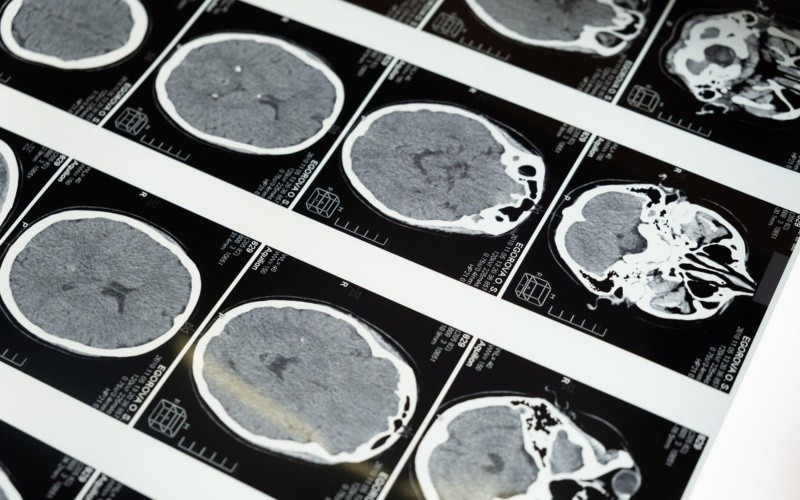

El nuevo modelo se practicó en 423 participantes. ESPECIAL/CORTESÍA MAYO CLINIC.

El nuevo modelo se creó según las medidas de la glucosa cerebral de la tomografía por emision de positrones con fluorodeoxiglucosa (FDG-PET, por sus siglas en inglés), realizada en 423 participantes del estudio que sufrían un impedimento cognitivo y tenían conexión con el Estudio de Mayo Clinic sobre el envejecimiento y con el Centro para la Investigación de la Enfermedad de Alzheimer en Mayo Clinic.

La tomografía por emisión de positrones con fluorodeoxiglucosa es una prueba por imágenes que muestra cómo aviva la glucosa ciertas partes del cerebro. Las afecciones neurodegenerativas, como la enfermedad de Alzheimer, la demencia de los cuerpos de Lewy y la demencia frontotemporal, por ejemplo, emplean la glucosa con patrones distintos.

El modelo condensa la compleja anatomía cerebral y relevante para los síntomas de demencia dentro de un marco conceptual y codificado por colores que muestra las zonas cerebrales relacionadas con los trastornos neurodegenerativos y las funciones mentales. Los patrones de las imágenes mostrados en el modelo corresponden a los síntomas del paciente.

Otra validación se obtuvo con la proyección de una gran cantidad de datos sobre el envejecimiento normal y los síndromes demenciales. ESPECIAL/CORTESÍA MAYO CLINIC.

La capacidad del modelo de predecir los cambios fisiológicos relacionados con la enfermedad de Alzheimer se validó en 410 personas. Otra validación se obtuvo con la proyección de una gran cantidad de datos sobre el envejecimiento normal y los síndromes demenciales que afectan la memoria, las funciones ejecutivas, el lenguaje, el comportamiento, el movimiento, la percepción, el conocimiento semántico y las capacidades visoespaciales.

Los investigadores descubrieron que tan solo 10 patrones pueden explicar el 51 por ciento de las variaciones en los patrones de consumo de glucosa dentro de los cerebros de pacientes con demencia. Cada paciente posee su propia combinación de estos 10 patrones cerebrales para la glucosa y dicha mezcla se relaciona con el tipo de síntomas que presenta. En la labor de seguimiento, el Programa de Inteligencia Artificial del Departamento de Neurología en Mayo Clinic, dirigido por el doctor Jones, utiliza estos 10 patrones para trabajar con sistemas de inteligencia artificial que ayudan a interpretar las exploraciones cerebrales de los pacientes evaluados por enfermedad de Alzheimer y otros síndromes afines.